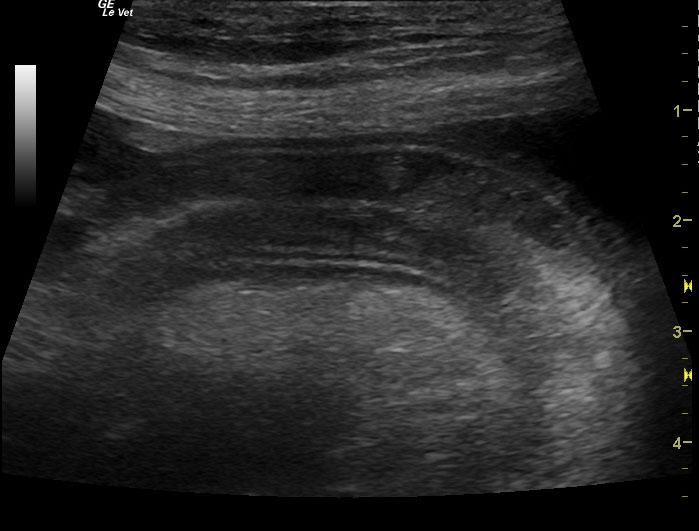

A 6-year-old female spayed Hound mix dog was presented for decreased appetite, increased drinking, and watery diarrhea for 4 days. Physical exam found soft, fluid filled bowels on abdominal palpation. An anti-diarrheal injection was administered, and the patient was discharged with oral anti-diarrheal medication, along with Tylan powder. Approximately 1 week later, the patient presented for persistent decreased appetite, lethargy, and watery stool. Physical exam found patient bright and alert, with pink mucous membranes, normal CRT, heart and lungs clear, a slightly distended abdomen, and no palpable masses found. Blood chemistry revealed hypoproteinemia, hypoalbuminemia, hypocalcemia, and hypocholesterolemia. CBC found high platelet count. Fecal was negative.